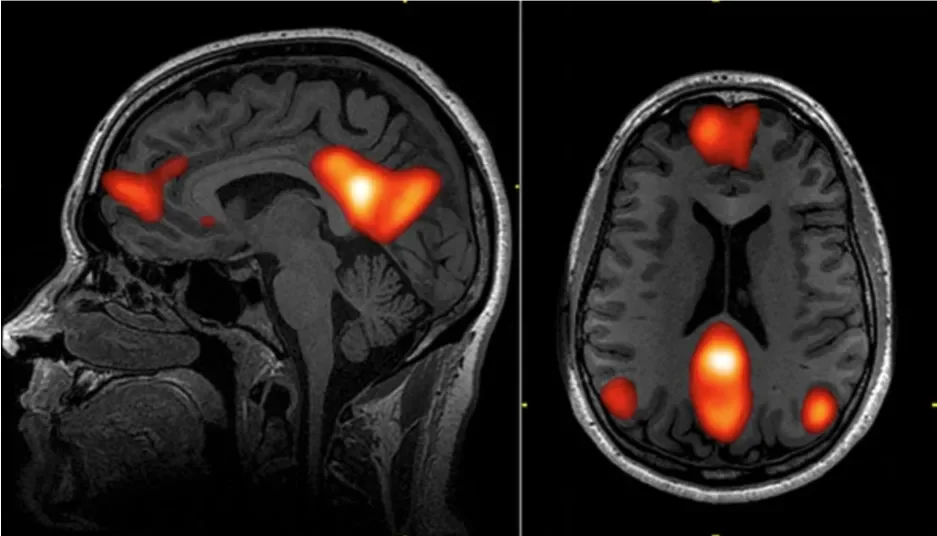

How psilocybin targets the brain's Default Mode Network to interrupt negative thought cycles and promote neuroplasticity for anxiety relief.